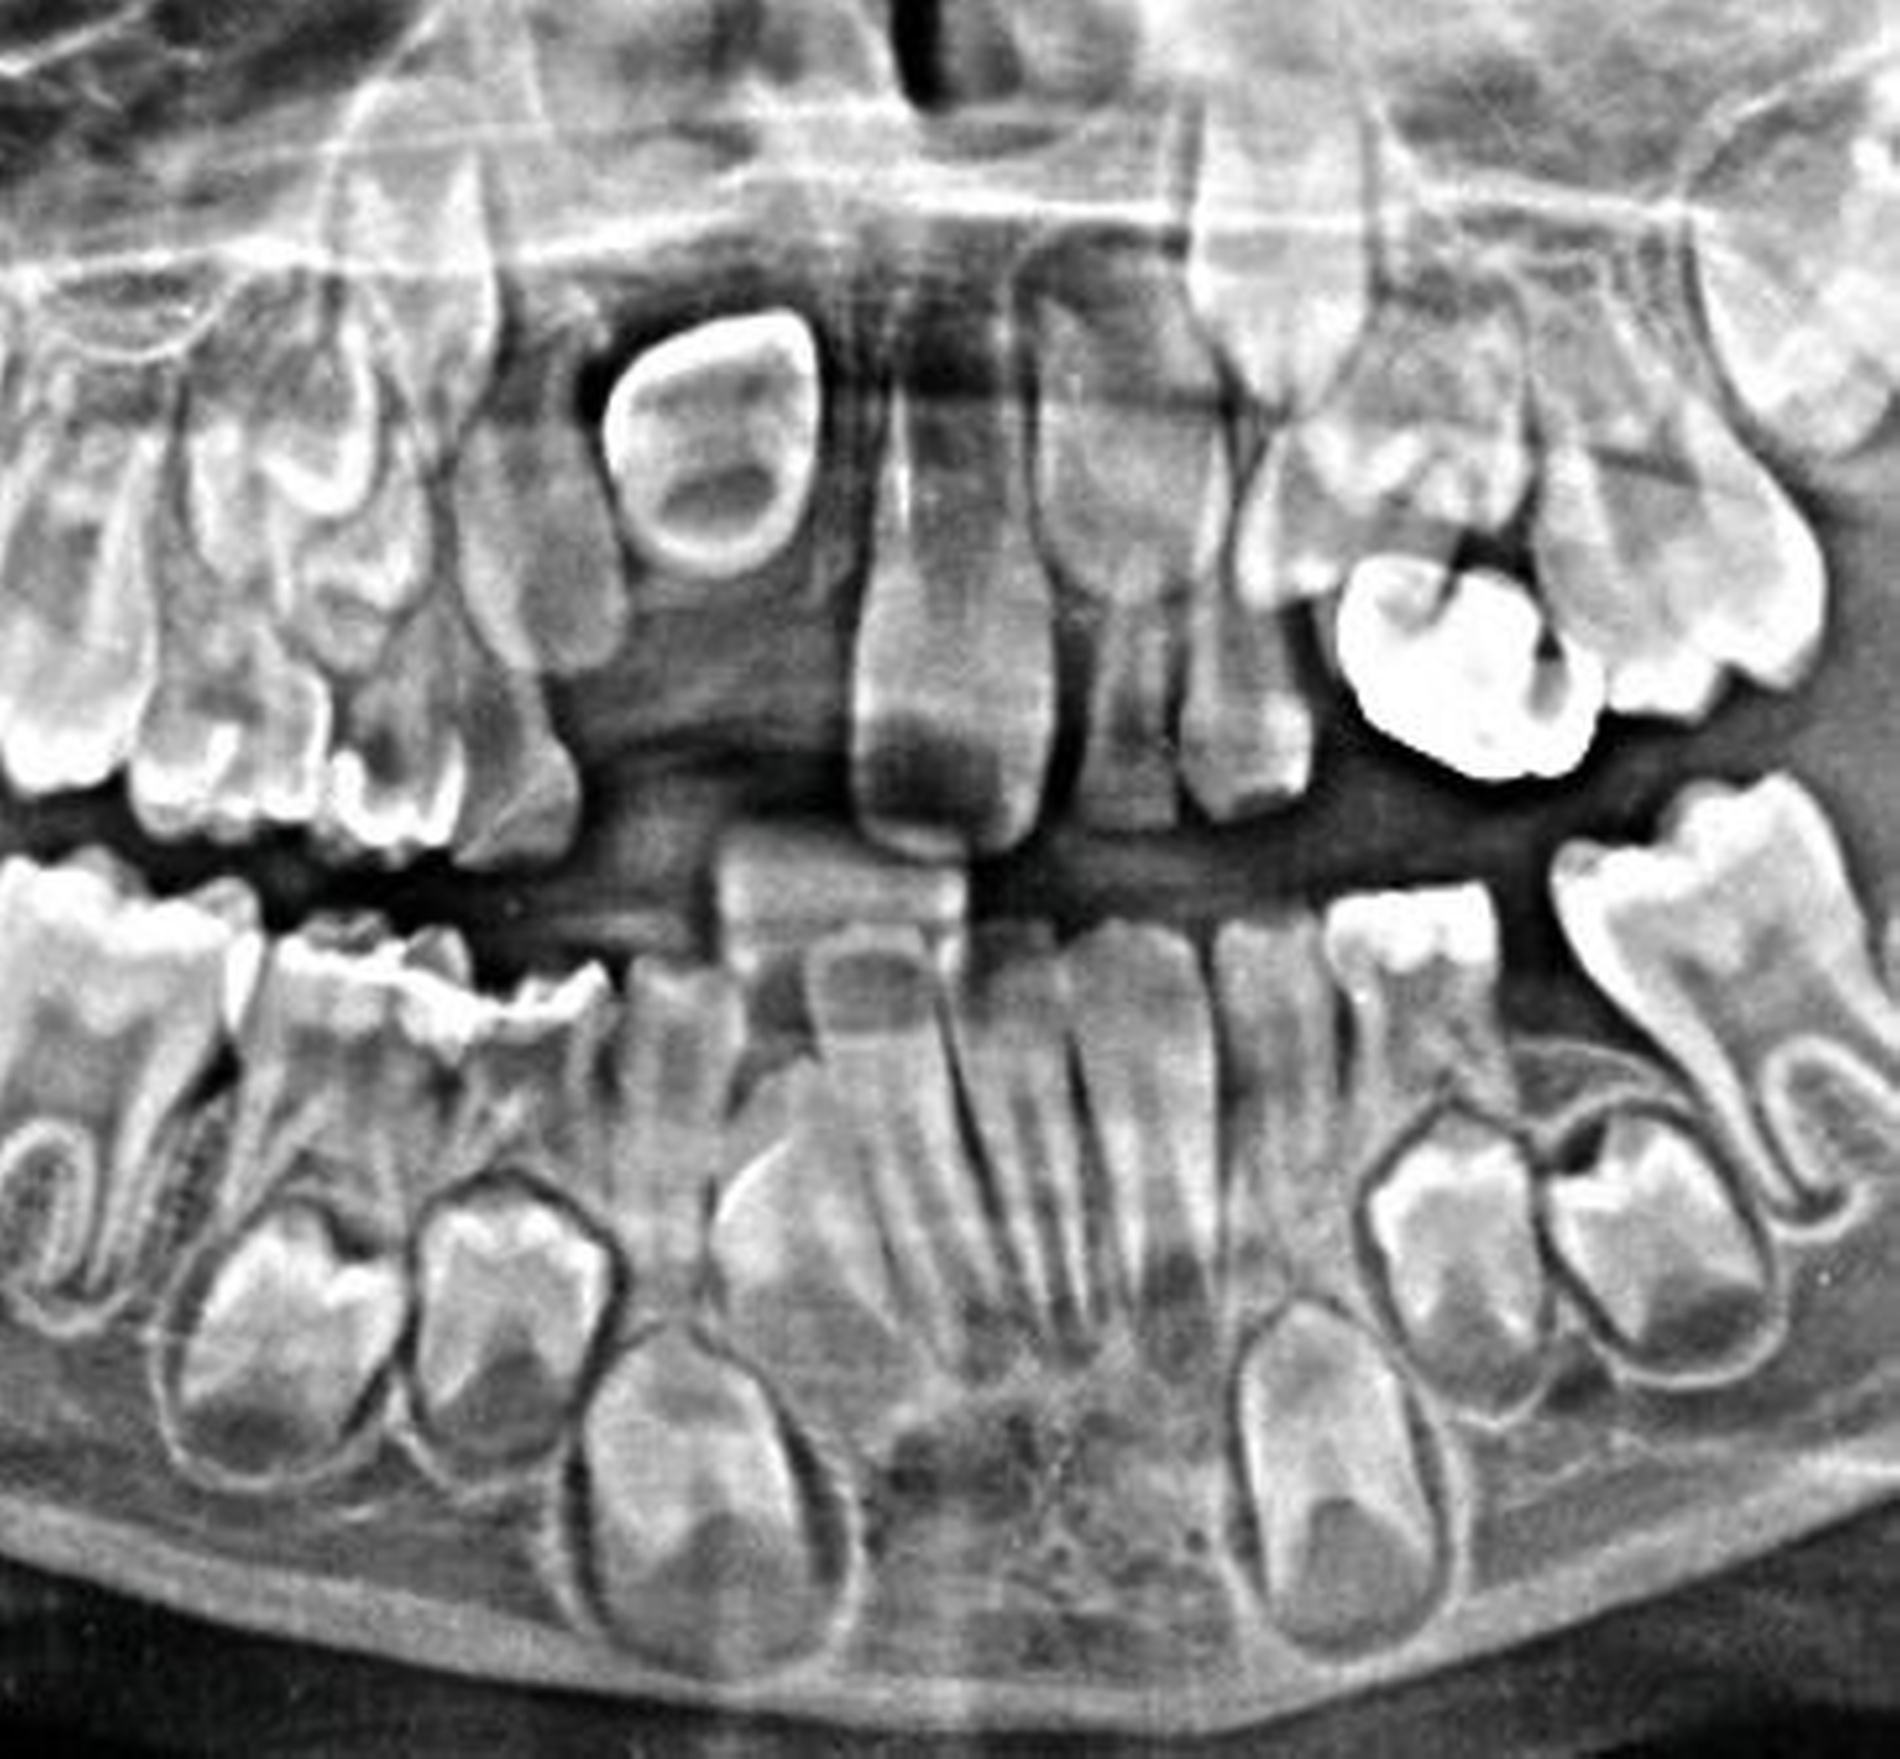

Abbildung 4 zeigt eine Milchzahn-Transplantation im frühen Wechselgebiss bei einem achtjährigen Mädchen bei nahezu vollständiger Ersatzresorption des Zahnes 11 nach Avulsion und Replantation. Trotz des sehr guten Zustands des Milchzahntransplants im Alter von zwölf Jahren entschied man sich in Rücksprache mit den Kollegen der Kieferorthopädie für die Prämolaren-Transplantation als eine zuverlässige Versorgung mit Überlebensraten von im Mittel 96,7 Prozent nach 8,75 Jahren [Akhlef et al., 2017]. Die Planung der Prämolaren-Transplantation sollte dabei immer in enger Absprache mit der Kieferorthopädie erfolgen, um zu klären, ob die Entnahme eines Prämolaren vertretbar und welche Entnahmestelle die geeignetste ist.

Da ein optimales Ergebnis vom Stadium der Wurzelbildung des Transplantats abhängt (ideale Wurzellänge 2/3 bis 3/4 Wurzelwachstum) hat die Transplantation ein „Zeitfenster“. Dieses kann nach oben geöffnet werden, indem man auch Zähne mit abgeschlossenem Wurzelwachstum transplantiert [Watanabe et al., 2010; Nolte et al., 2011; Chung et al., 2014]. Allerdings wird dadurch die Notwendigkeit einer späteren Wurzelbehandlung erhöht. Nach unten lässt sich das Zeitfenster erweitern, indem man auf einen Milcheckzahn als Transplantat zurückgreift [Pohl et al., 2008; Tschammler et al., 2015, Hoss et al., 2021]. In diesem Fall entfällt das kieferorthopädische Schließen der Transplantatlücke.

Als Zwei-Phasen-Transplantationskonzept wird die Kombination aus Milchzahn-Transplantation im frühen Wechselgebiss und Prämolaren-Transplantation im späten Wechselgebiss bezeichnet [Nolte et al., 2017]. Das Besondere an dieser Methode ist, dass die traumatisierten Kinder mit Zahnverlust zeitnah ästhetisch rehabilitiert werden können und dabei das noch erhebliche, zu erwartende vertikale Wachstum des anterioren Kieferabschnitts zuverlässig unterstützt werden kann.